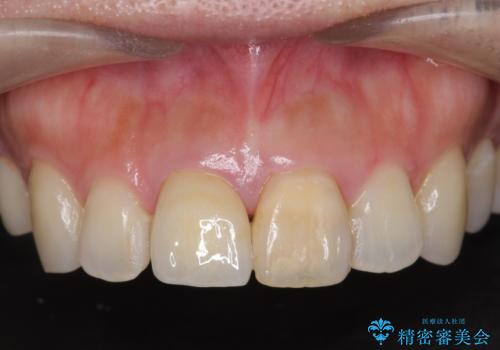

天然歯を再現したリアルな仕上がりに満足いただくことができました。

オールセラミッククラウン スペシャルプランは細やかな色調の再現に優れ、目立つ前歯の審美的な仕上がりがより達成されやすいプランです。